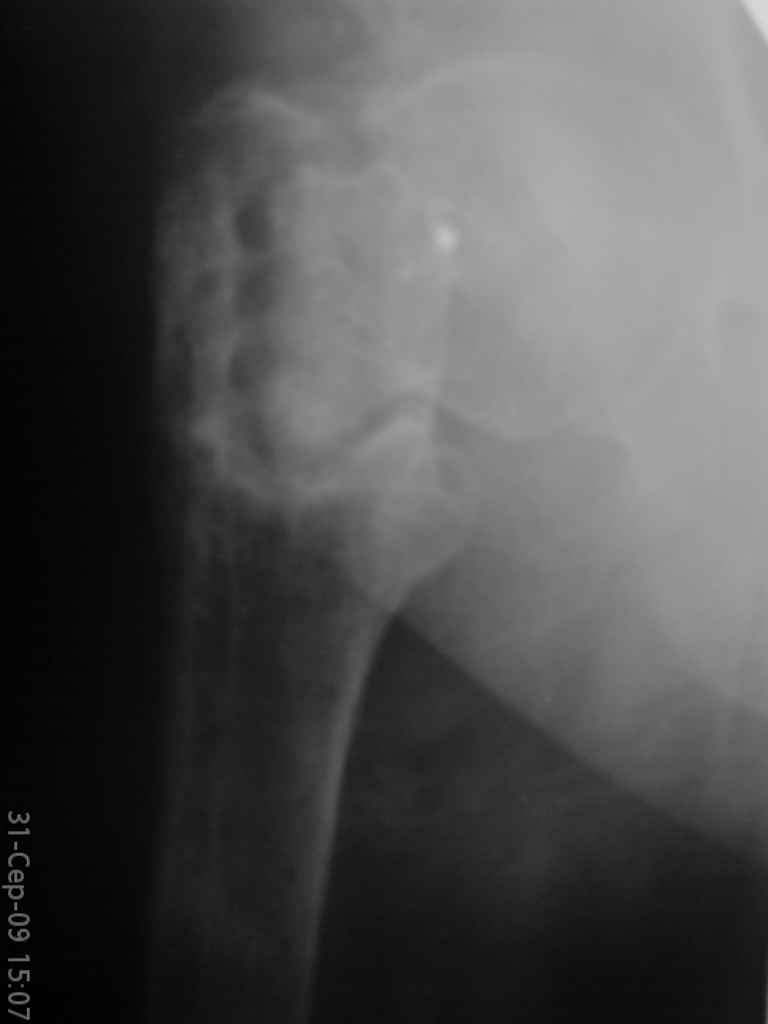

Больная, 62 года,жалуется на боли,неопорность левой ноги. Ходит с помощью костылей, укорочение ноги 3 см. Два года назад была оперирована кокой-то накостной пластиной, пластину удалили 4 мес назад. Вопрос такой: предлагать эндопротезирование или делать МОС (что-то по типу стержня Gamma)?

За качество снимков извините, по данным МРТ - головка живая